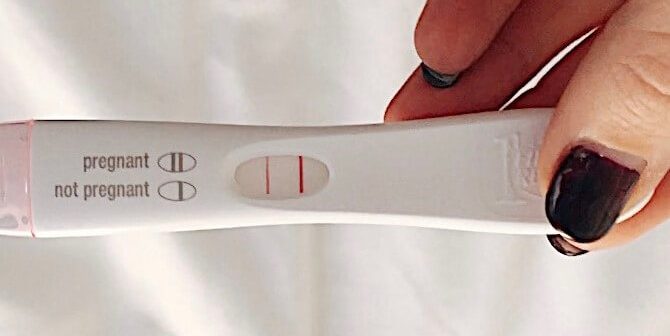

Banyak diantara pasangan suami istri yang merasa kecewa setelah awalnya sangat bahagia melihat dua garis biru di test pack. Namun, ketika diperiksakan ke dokter atau bidan ternyata mengalami kehamilan kosong.

Wanita yang mengalami ciri ciri kehamilan kosong akan mengalami tanda-tanda kehamilan seperti pada umumnya seperti terlambat datang bulan, tes urine positif, hingga morning sickness. Hal ini karena proses awal yang terjadi ketika kehamilan ini seperti kehamilan normal pada umumnya.

Banyak wanita yang mengalami blighted ovum mengira jika kehamilan mereka berjalan normal seperti pada umumnya karena tingkay hCG mereka juga mengalami peningkatan.